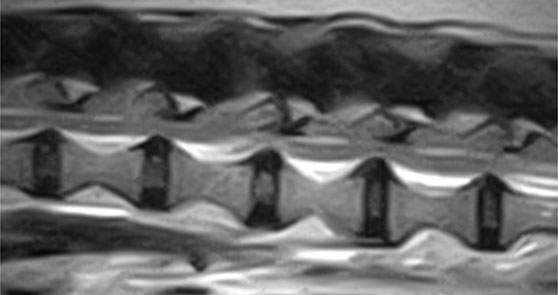

呼吸器疾患

気管・気管支虚脱に対して手術時侵襲性の少ない気管ステントを用いています。以前のもののような合併症は少なく、手術時間が非常に短く済みます。

気管ステント設置術